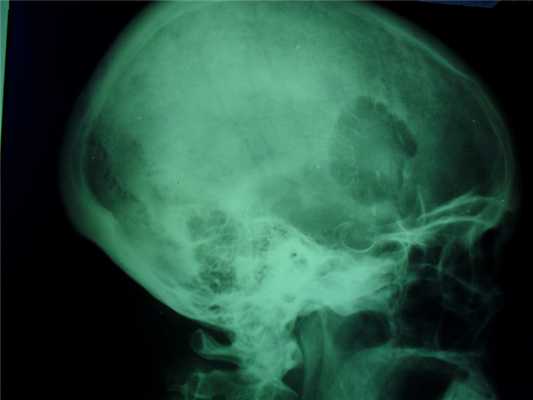

При локализации гемангиомы в плоских костях свода черепа происходит:

- вздутие кости и разрушение коркового слоя, надкостница приподнимается опухолью,

- характерен структурный рисунок - из центра опухоли к ее поверхности лучеобразно или веерообразно рассыпаются тонкие и более грубые костные балки.

Внутрикостная гемангиома черепа может сопровождаться головной болью, которая обуславливается постоянным раздражением мозговых оболочек. Иногда можно нащупать на черепе небольшую довольно плотную выпуклость - в этом случае безотлагательно посетите специалиста и пройдите назначенную диагностику. В АЦМД-Медокс успешно диагностируются гемангиомы любой локализации при помощи МРТ и СКТ.

При помощи рентгена: довольно слабо. Диагностированию поддаются в основном уже крупные гемангиомы или те, которые деформируют внешний контур кости.

Гемангиома в плоских костях черепа - не частое образование, которое располагается преимущественно в диплоическом слое. Имеется разряженное строение губчатого вещества и толстые костные трабекулы, радиально расходящиеся в стороны. Очаг разряжения губчатого вещества в толще диплоического слоя определяется как зона↓плотности на КТ (стрелка на рис.1221) и↑МР-сигнала на Т2 и Flair (головки стрелок на рис.1219-1221).